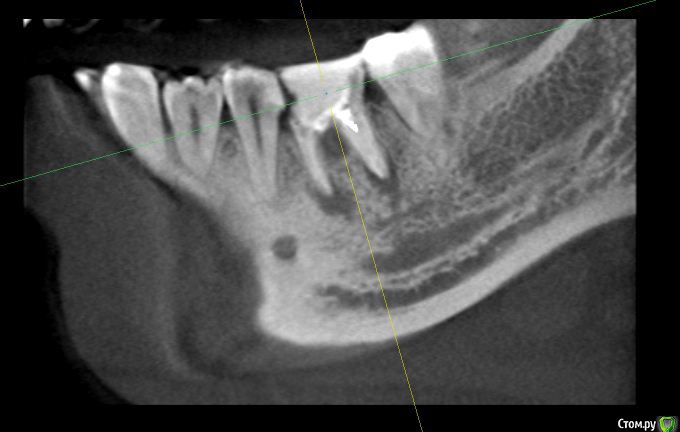

alex_ts Опубликовано 7 ноября, 2016 Поделиться Опубликовано 7 ноября, 2016 (изменено) Здравствуйте. Периодически беспокоит нижняя 6ка, 3 года назад она была на 3/4 разрушена и там стояла "металлическая" черная пломба, от которой зуб приобрел синий оттенок. На мой вопрос что его наверное надо удалять, стоматолог на меня тогда удивленно посмотрела и сказала что корни хорошие и ничего удалять не надо. Тогда же она поставила очень большую пломбу, сказав что это не на долго и так или иначе придется одевать коронку. Сейчас зуб время от времени побаливает и иногда кровит. Сходил в клинику, сделали кт зуба. Врач сказала что варианта 2, либо долго и сложно лечить этот зуб и протезировать, но без гарантии, так как там затемнение в области фуркации, либо удалять и ставить имплант. Что вы порекомендуете в данной ситуации? Спасать зуб или лучше будет избавиться от него? Мч, 24 года Изменено 7 ноября, 2016 пользователем alex_ts Ссылка на комментарий

dok1 Опубликовано 8 ноября, 2016 Поделиться Опубликовано 8 ноября, 2016 И присмотритесь к следующему зубу. Ссылка на комментарий

dok1 Опубликовано 8 ноября, 2016 Поделиться Опубликовано 8 ноября, 2016 К семёрке. Следующий двухкорневой. Ссылка на комментарий

anvladd Опубликовано 8 ноября, 2016 Поделиться Опубликовано 8 ноября, 2016 Кариес под пломбой Ссылка на комментарий